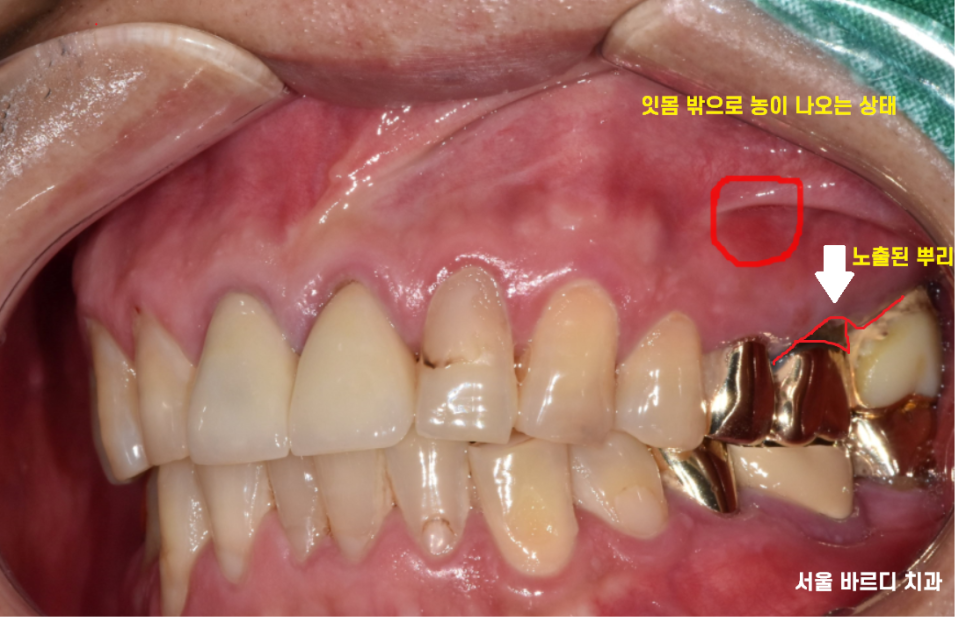

23.07.06

구강 내 사진입니다.

눈으로 보이는 부분에서도

좋지 않은 것은 마찬가지..

하남 미사 치과에서는

자연치아를 살리는 것을 추구하기 때문에

3단계의 단계적 검사 방법을 사용했습니다.

안타깝지만 뽑아야 했는데요.